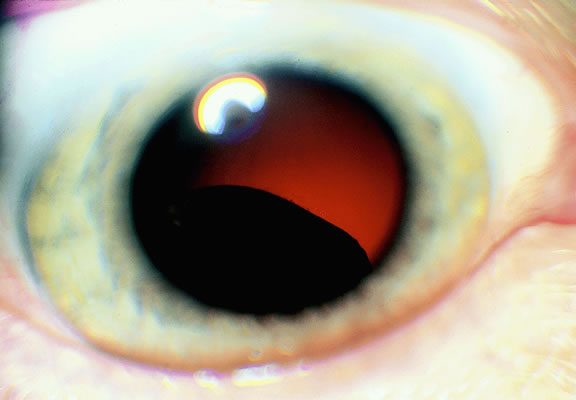

The ready visibility of many iris melanomas leads to their diagnosis at an earlier age and a smaller size (Fig. 10). Iris melanoma typically is discovered when a patient or his or her physician detects a focal pigmented blemish. Higher grade iris melanomas, or ciliary body tumors that invade the anterior chamber, can seed the iris and anterior chamber causing acquired hyperchromic heterochromia iridum (Fig. 11). Secondary glaucoma often accompanies the change in iris color. Not infrequently, the underlying diagnosis may be overlooked and the patient is treated for glaucoma, especially when a melanoma is nonpigmented or confined to the periphery of the iris or the trabecular meshwork.

Fig. 11. Patient with iris heterochromia caused by diffuse iris melanoma.

Iris melanoma is relatively rare, constituting between 4% to 15% of uveal melanomas in various series.93 The studies with higher reported incidences may reflect inclusion of nevi. Iris melanomas differ in some respects from tumors of the posterior segment. Most are low-grade spindle cell tumors (Fig. 43). However, iris melanomas with epithelioid cells occasionally are encountered (Fig. 44). Many pigmented iris tumors actually are nevi,94 and relatively few of these enlarge when observed. Several studies have shown that the risk of enlargement in 5 years is only 5% to 6% after a subset of promptly treated lesions is excluded.95,96 One study showed that iris tumors are likely to be considered melanomas and be treated promptly if the basal diameter is greater than 3 mm, pigment dispersion or prominent tumor vascularity are present, the intraocular pressure is elevated, or there are tumor-related symptoms.95 The mean age of patients with iris melanomas is about 10 years younger (age 43 years) than the age of patients with posterior segment melanomas.97 The prognosis of iris melanoma is also relatively favorable compared with tumors of the posterior segment. Shields and coworkers97 studied 169 patients with histologically confirmed iris melanoma and found that distant metastases developed in 5% at 10-years follow-up. The relatively small size of most iris melanomas probably is a major factor in their good prognosis. The prognosis of iris melanomas actually may be similar to posterior segment tumors of similar size and cell type. Diffuse iris melanomas that cause heterochromia iridis and secondary glaucoma are a rare but clinically important group of iris tumors.98,99 Many diffuse iris melanomas are higher grade tumors that contain epithelioid cells, which are poorly cohesive and prone to aqueous dispersal. Glaucoma surgery should be avoided in such cases. It invariably fails and puts patients at greater risk for extraocular extension and metastasis.100